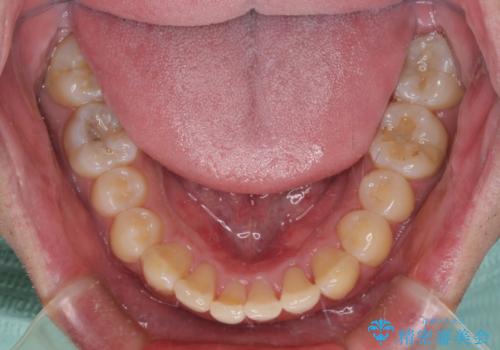

- 上下前歯のデコボコを気にして来院された患者様です。

前歯のデコボコ以外に左側の奥歯の咬み合わせに問題がありましたが、価格を抑え、短期間で気になる前歯を治したいとのことでした。

写真より左側臼歯の咬合がタイトではないことが分かりますが、こちらは保定期間に徐々に咬合させていくこととしました。